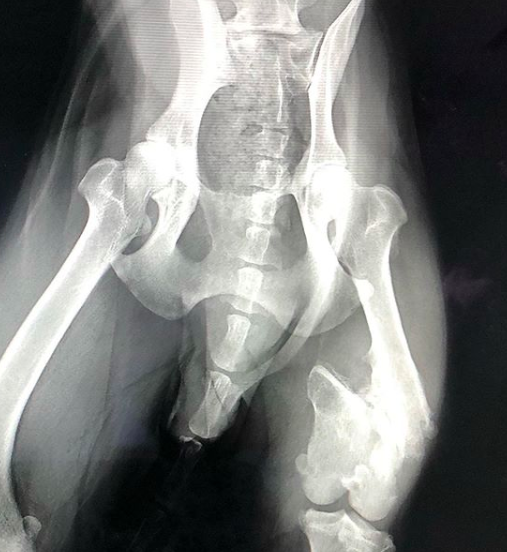

血液検査の結果、貧血も出始めていて、腫瘍の成長がはやく、自壊することを考慮に入れ、手術するのであれば、少しでも早くに…と言うことで、そのまま手術になりました。跛行のある左後脚は、古傷で大腿骨が酷く骨折したまま放置されたことが原因でした…。そのため、左右の脚の長さが違ってしまっていますが、古傷なので手術はしませんでした。鼻血は、メンバー宅到着時から止まっていますので、様子見することになりました。(もし腫瘍の転移だとしても、取ることはしないので)